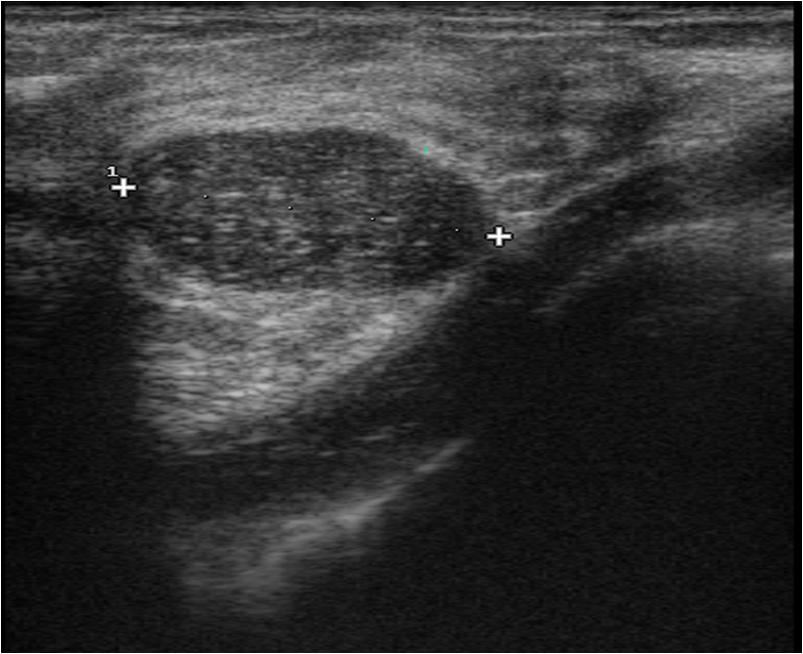

Ultrasonography can help in their differentiation; can depict anechoic cystic lesions (Picture17.) or solid masses (Picture 18.). These lesions usually each have a smooth, sharp edge and echo-enhancement can appear behind them. Rarely, cysts contain tumors. (Picture19.).

Ill-defined margins, with uneven contours and blurred edges are usually characteristic of malignant lesions. During ultrasound examination echo-attenuation occurs frequently behind these inhomogeneous hypo-echogenic masses (Picture 20).